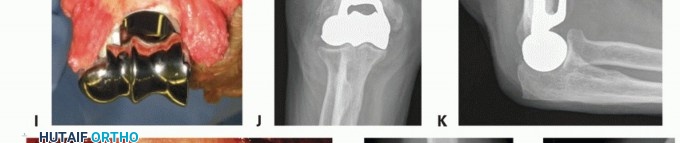

During a distal humeral hemiarthroplasty (DHH), the bony preparation is focused on the medial and lateral columns. When these are not intact, reconstruction with temporary K-wire fixation to judge length and more definitively either wire or tension band fixation or plate and screw fixation should be attempted (TECH FIG 4I-N). The preservation and reconstruction of the columns are especially important when using an implant without an anterior flange.

TECH FIG 4 • (continued) I-K. Latitude DHH. I. Intact medial and lateral humeral columns, with a red vessel loop loosely around the ulna nerve. J. AP radiograph demonstrating the trochlea and capitellum correctly sized for the host, greater sigmoid notch of the ulna, and the radial head. K. Lateral radiograph demonstrating a well-aligned radio capitellar joint and osseous integration of the anterior flange. L-N. Sorbie DHH. L. Fractured medial and lateral columns were reconstructed with K-wires, prior to implant insertion. M. AP radiograph demonstrating a well-seated Sorbie implant with healed medial and lateral columns. N. Lateral radiograph demonstrating a well-aligned radiocapitellar joint with posterior heterotopic ossification in the traumatically injured triceps muscle.